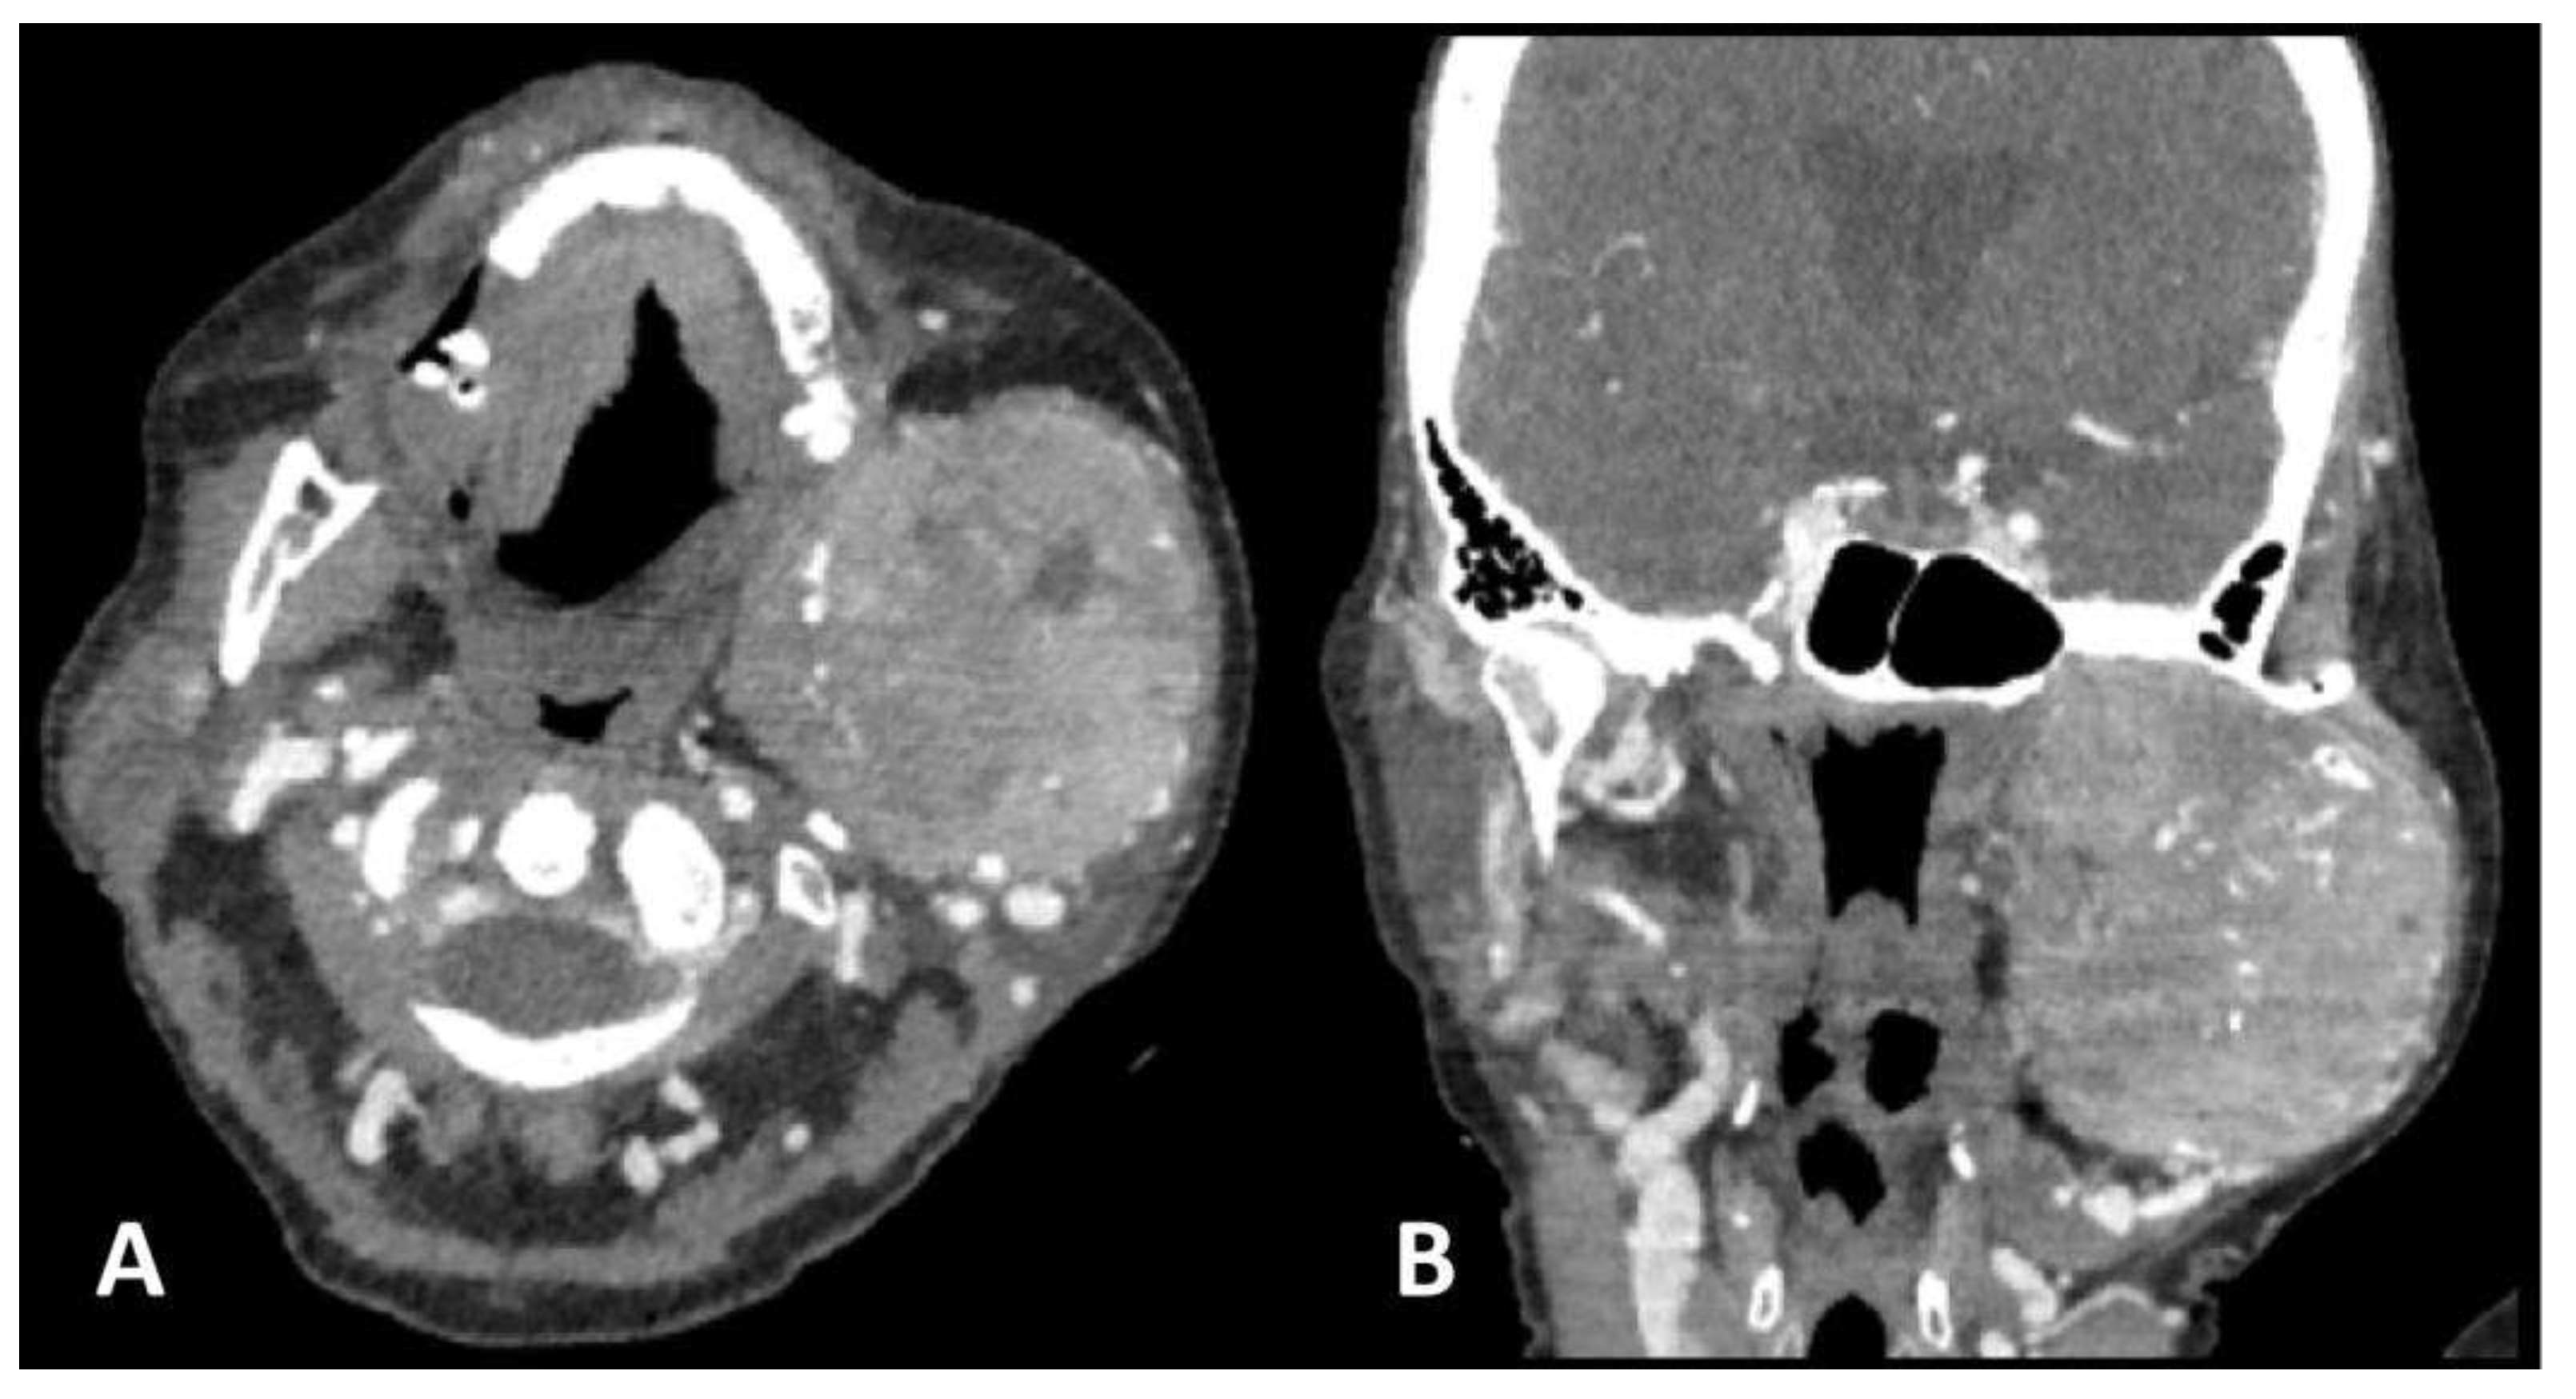

Two months after the initial diagnosis and subsequent liver resection, the patient was admitted to a COVID hospital due to a positive PCR COVID-19 test and the chest X-ray findings of a bilateral pneumonia. At the admission, she reported a diffuse, firm, and painless swelling of the left jaw which she noticed a week prior to admission and thereafter a neck CT was ordered. The neck CT demonstrated a large osteolytic soft-tissue mass in the left mandibular angle and ramus, spreading to the temporal fossa and parotid area occupying the space from the skull base to the submandibular area. The mass displayed heterogeneous and intense contrast enhancement, along with osteolytic bone changes and infiltration of the masticatory muscles (Figure 2).

Typically, the radiologic presentation of HCC bone metastasis is an osteolytic soft-tissue mass, commonly hypervascular as the primary HCC itself [16]. In that respect it is understandable why the lesion itself is prone to bleeding [15,17]. Due to the afore mentioned bone metastasis of HCC characteristics, special care needs to be taken while performing biopsy, therefore, percutaneous core biopsy or fine needle aspiration (FNA) biopsies are favorable compared to incisional biopsies [7]. This characteristic imaging presentation of bone HCC metastasis was consistent in the presented patient, as evidenced by CT performed in the investigation of a painless jaw swelling. The neck CT demonstrated a large, infiltrative, hypervascular, osteolytic lesion in the left mandible ramus. Subsequently, percutaneous core biopsy of the left jaw mass, as well as PH report proved it to be the HCC metastasis in the left mandibular bone.

Figure 2. Axial (a) and sagittal (b) images of contrast-enhanced neck CT scan show a large, lobulated, intensively opacified osteolytic soft-tissue mass in the left mandible angle and ramus, extending from the base of the skull to the mandibular angle. Infiltration of masticatory muscles is observed as well.